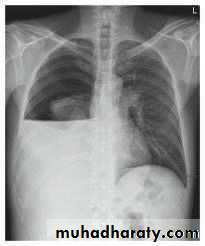

Pneumothorax

!! pneumothorax